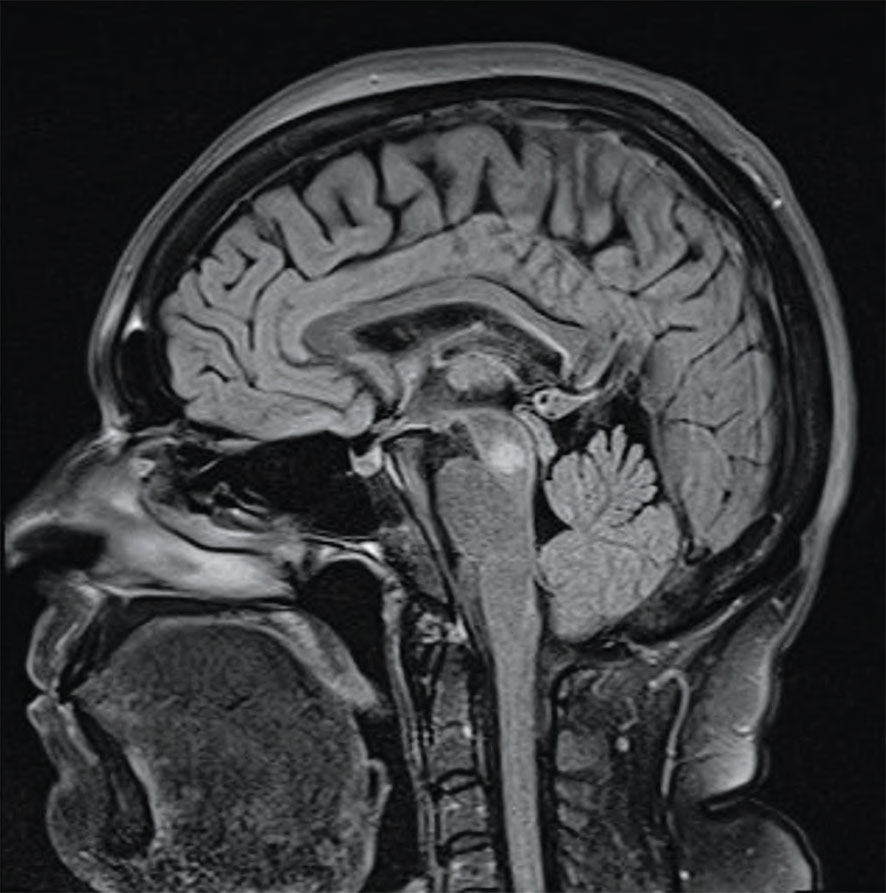

Fallbeskrivning Perkutan mikrovågsablation förbättrade trombocytnivån hos patient i nedre tonåren med förstorad mjälte